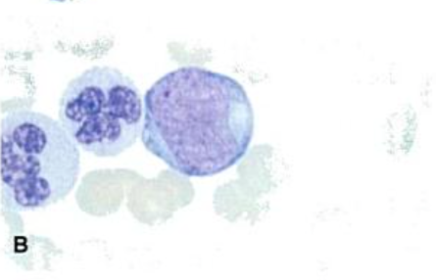

Fuente: Rodak, E. (2004). Hematología: Fundamentos y Aplicaciones. (2da ed.). Madrid, España: Editorial Médica Plasmocito Morfológicamente, son más grandes que los linfocitos B independientes del antígeno, son redondos con un citoplasma abundante y gránulos azurófiros, un núcleo periférico ovalado basófilo (Rodak, 2004).

Es el linfocito B completamente maduro y funcional, presenta IgM e IgD en su membrana, en este estado poseen especificidad y son completamente dependientes del antígeno (Rodak, 2004). Fuente: Rodak, E. (2004). Hematología: Fundamentos y Aplicaciones. (2da ed.). Madrid, España: Editorial Médica